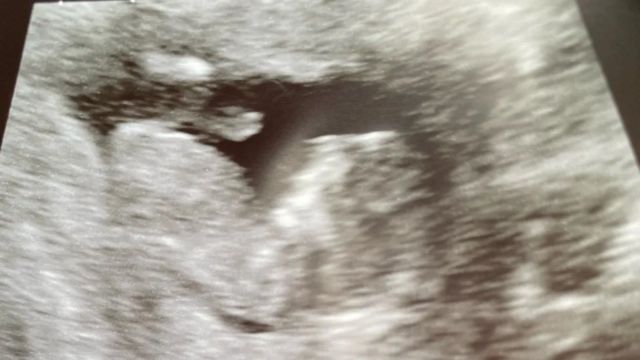

Пять положительных тестов на беременность и экстренный осмотр в больнице подтвердили, что Бет и ее муж, 31-летний Шон, ждут третьего ребенка.

Автор фото, BETH MCDERMOTT